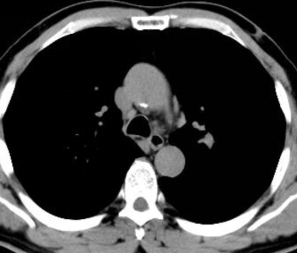

图1 术前胸部 CT 肺窗,提示左肺固有上叶尖后段外周小结节病灶

患者因体检发现左肺结节就诊,胸部CT提示左肺固有上叶尖后段存在微小病灶,病灶位于肺野外周,远离中央气道,普通支气管镜无法直视及抵达病灶,常规活检手段阳性率极低,难以明确病理性质。